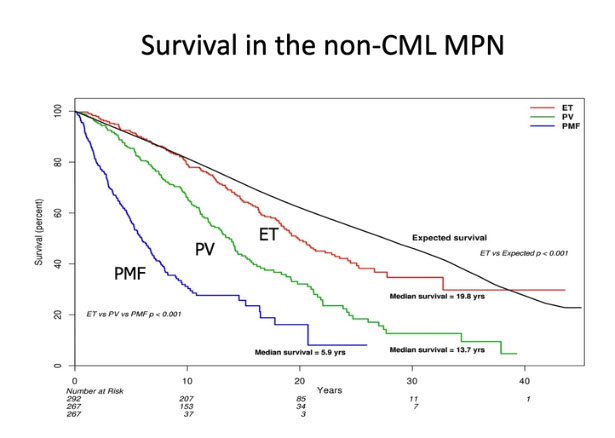

Px

Survival from months to decades depending on the stage at first diagnosis

Death from BM failure, portal HTN, thrombosis, CHF and AML

- 5%-8% transform into AML.

Survival >10 years common

- most pts die from thrombosis or hemorrhage, ~20% get MDS or AML (which increases with use of certain cytotoxic therapies)

Px: occasional thrombotic or bleeding outsomes

- excellent long-term survival,

- do not develop marrow fibrosis

- <5% progression to AML (little if any increase than the general population)